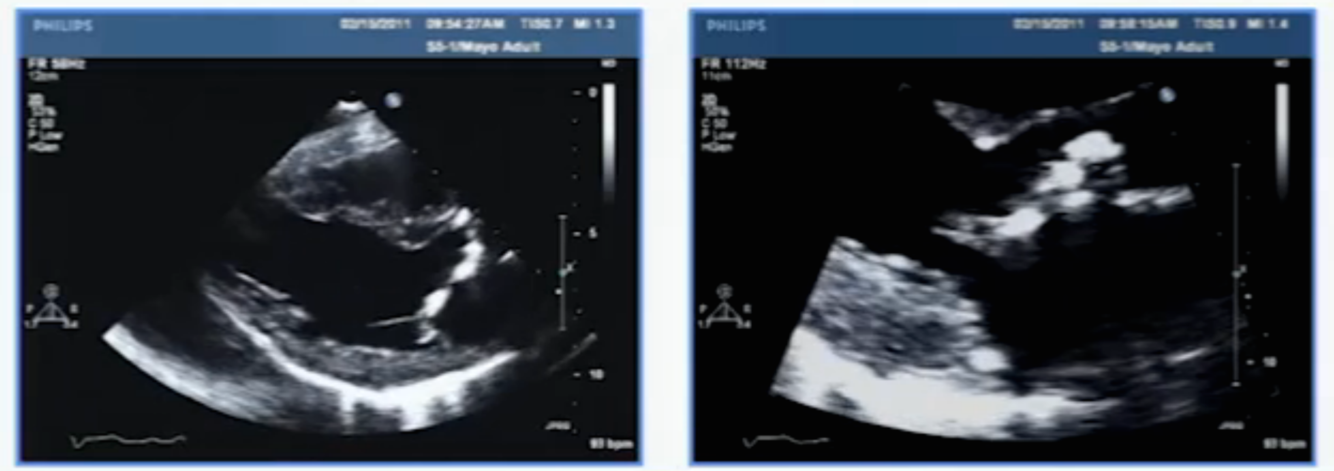

dx?

carcinoid